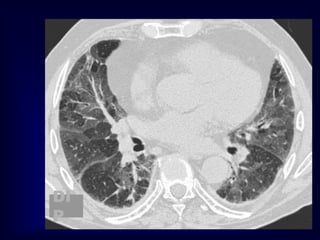

DECREASED

LUNG

ATTENUATION

Lung Cysts

Pulmonary fibrosis (Honeycombing)

Lymphangiomyomatosis

Langerhanscell histiocytosis

Lymphocytic Interstitial Pneumonia (LIP)

The most likely diagnosis is:

A. Metastatic tumor of unknown primary

site.

B. Sarcoidosis.

C. Langerhans cell histiocytosis.

D. Idiopathic pulmonary fibrosis.